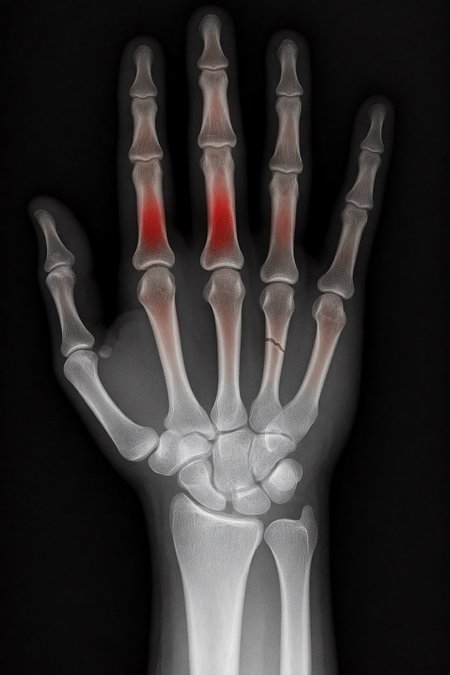

2. Ask: “Make marks where there is a fracture”.

Test results:

False positives ≈ 24%

Fracture detection ≈ 20%

Sensitive mode (more detection, lots of noise)

False positives ≈ 80%

Fracture detection ≈ 86%

Even more aggressive settings (e.g. rk beta57 to denoise 1.0) reach the absurd: 100% false positives and 100% detection: it paints everything red and almost hits all fractures beyond marking healthy areas, for an untrained eye.